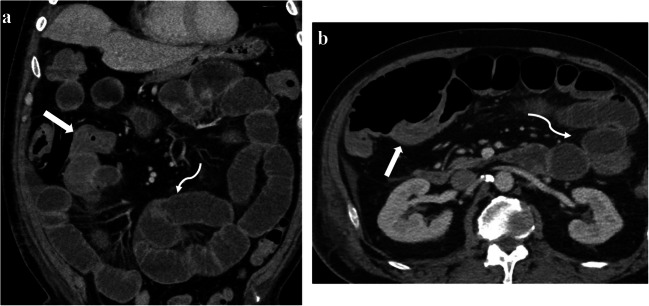

Fig. 4.

Sixty-nine-year-old male admitted for coronavirus disease 2019 pneumonia with acute respiratory distress syndrome who received ventilation and vasopressor treatment. CT was obtained due to increasing abdominal distension. Coronal (a) and axial (b) images of contrast enhanced CT demonstrate diffuse wall thickening along the terminal ileum (straight arrows in a and b) and mild diffuse dilatation of the fluid-filled proximal small-bowel loops (curved arrows in a and b), suggestive of terminal ileitis and secondary bowel dilatation. Patient was conservatively managed and discharged approximately 2 weeks after